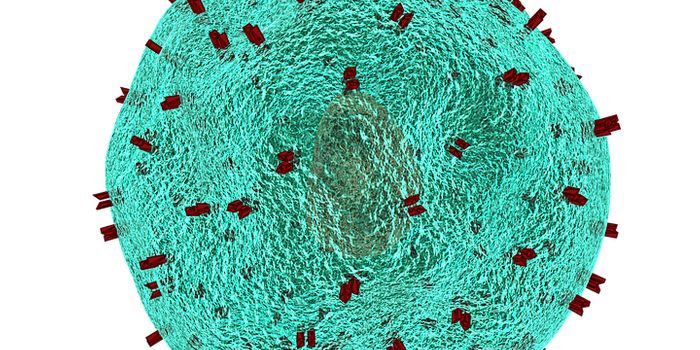

MAR 21, 2024ImmunologyAcute myeloid leukemia (AML) is a rare and aggressive hematologic malignancy. AML progresses rapidly and is indicated by ...